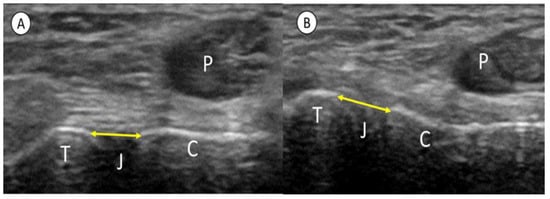

2.2. Procedures